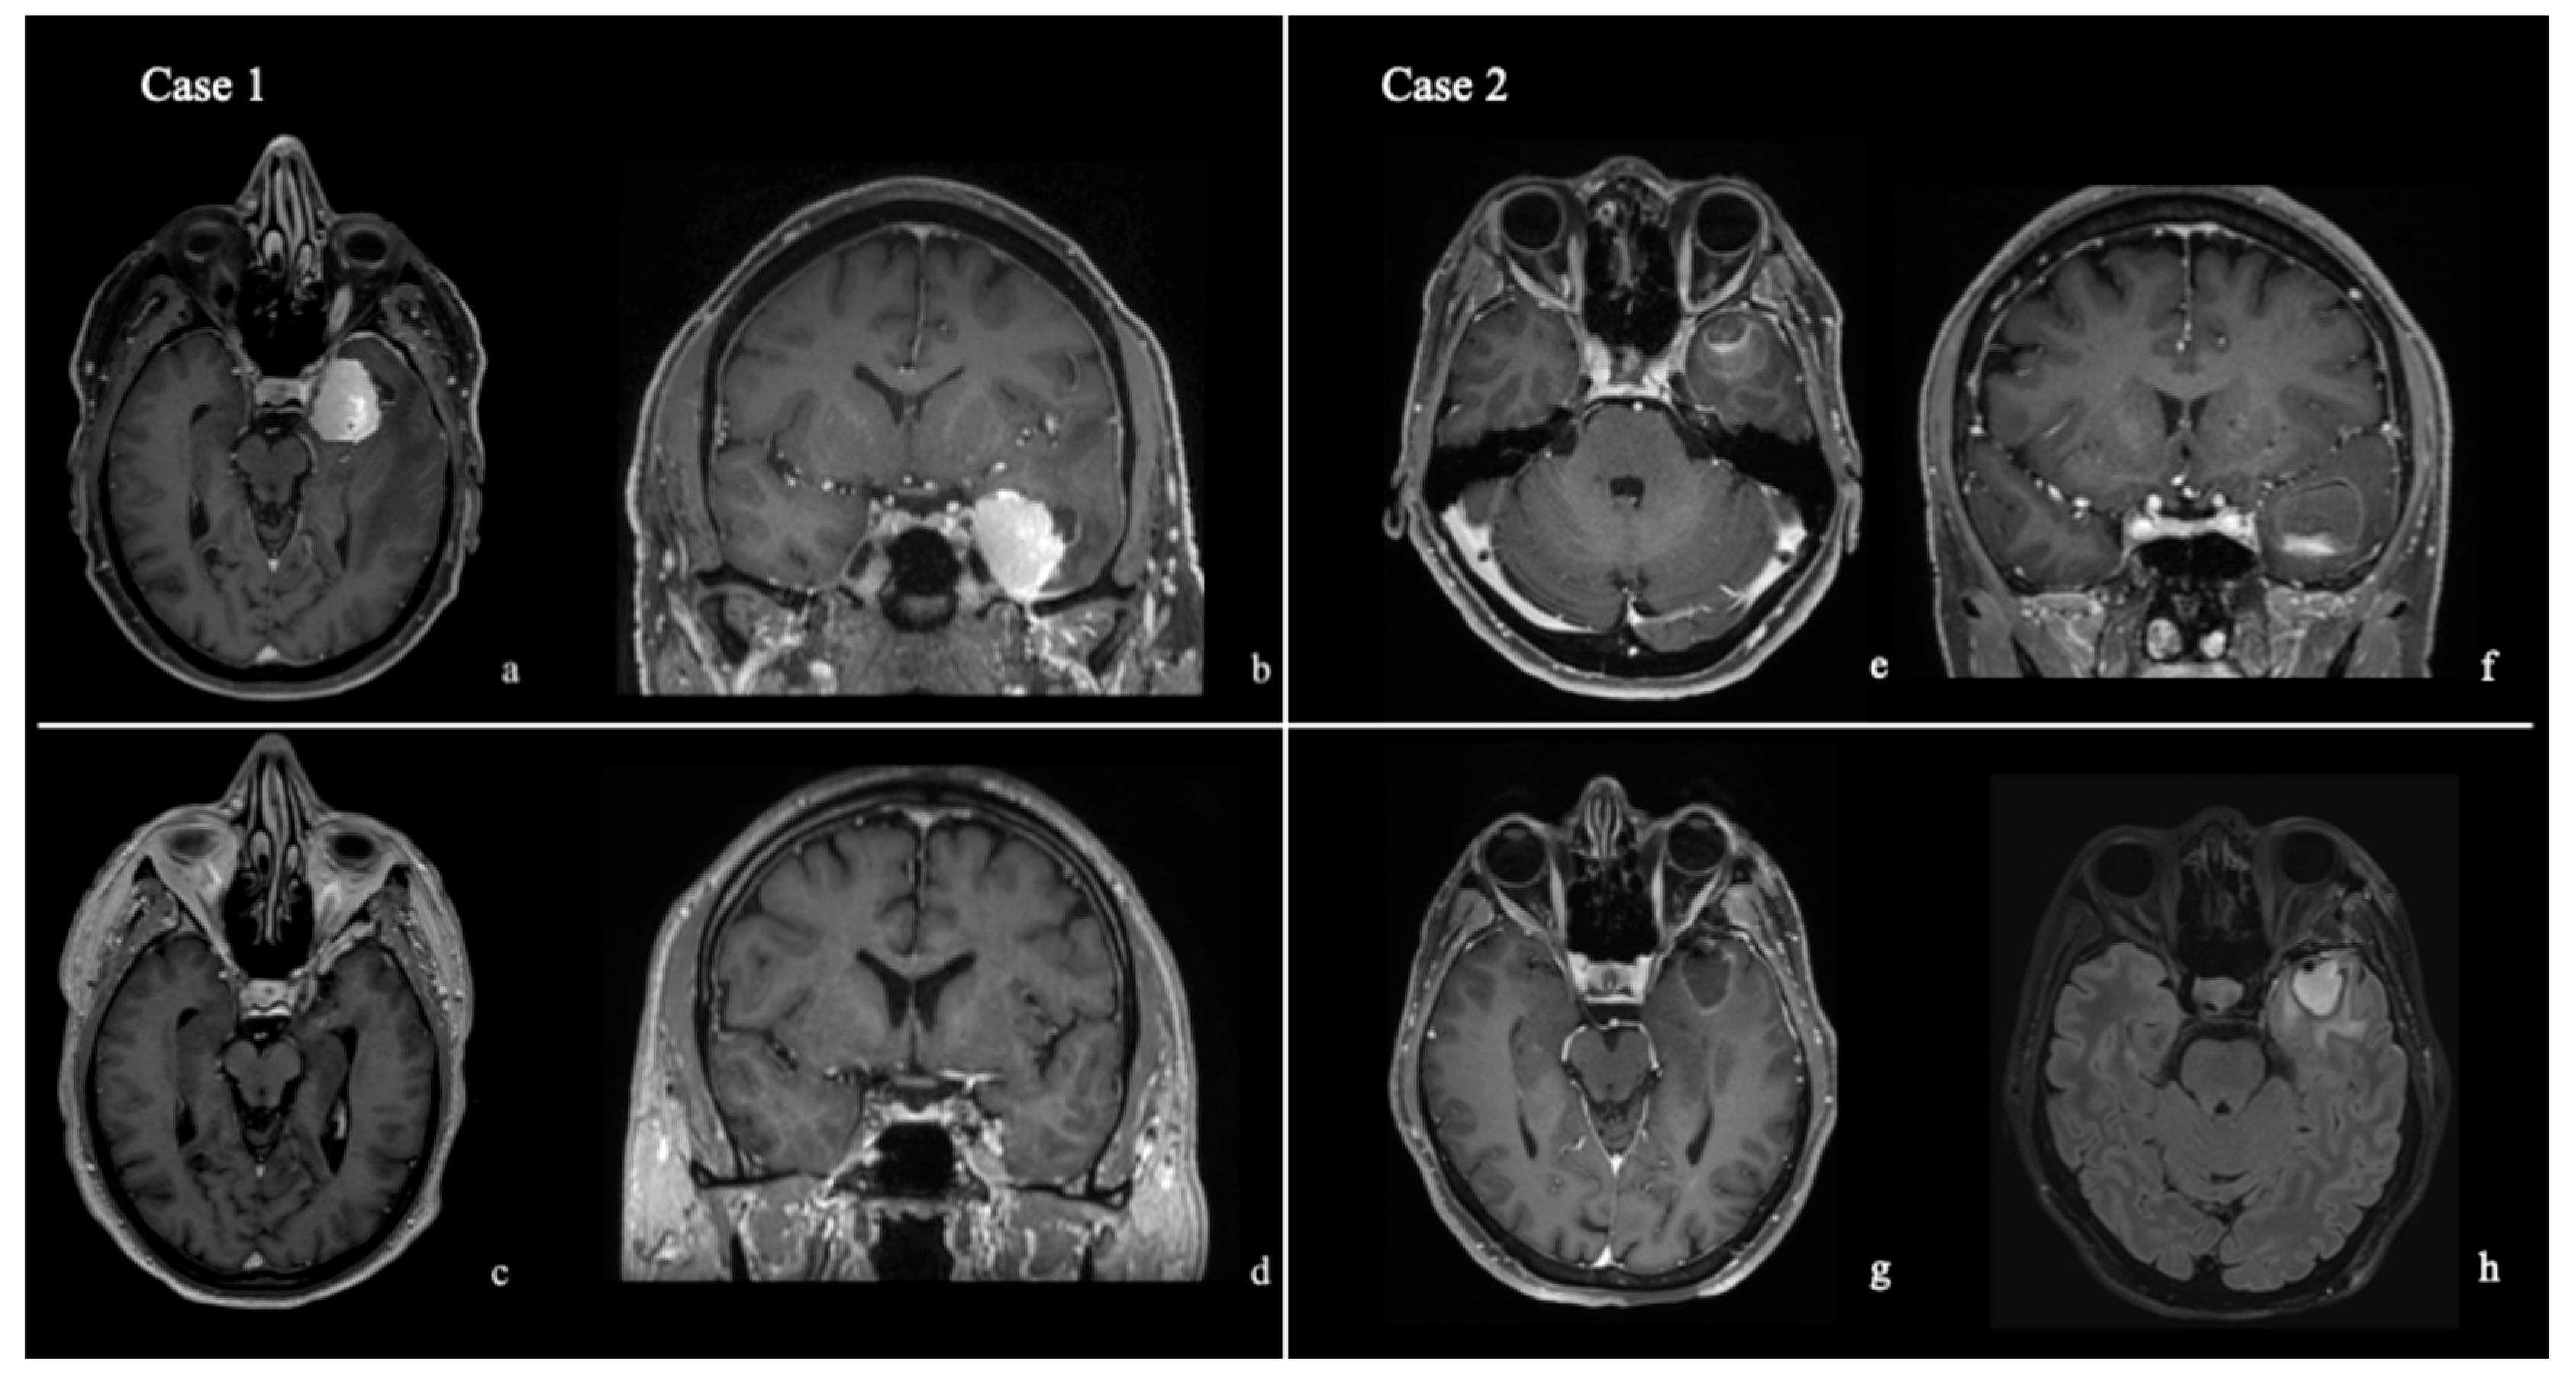

3. Results